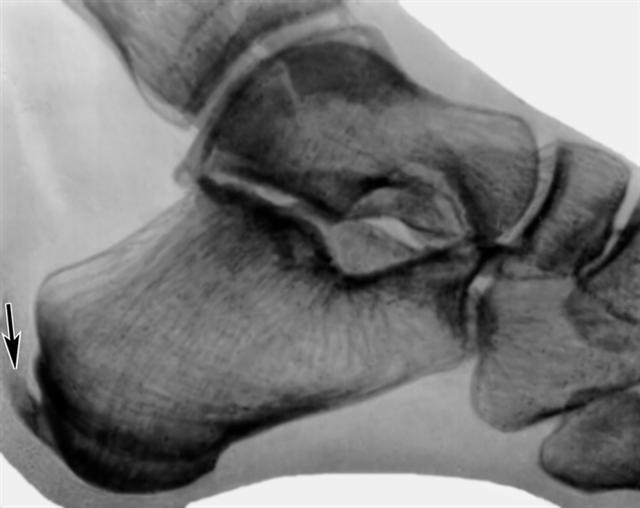

Рис. б). Рентгенограмма стопы (боковая проекция) при задней пяточной шпоре (указаны стрелками).